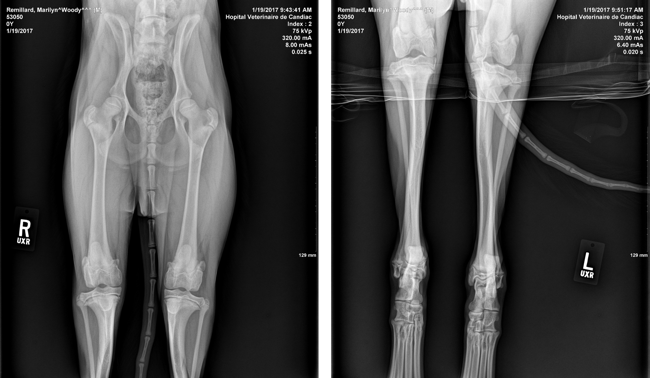

Depuis environ 1 mois, il a commencé à marcher d'une drôle de façon. Il marche en canard, on dirait qu'il tente d'utiliser le moins possible ses pattes arrières. Quand il court, il court en lapin. Nous sommes allé voir un vétérinaire. Celui-ci était persuadé qu'il s'agissait d'un problème de hanches mais en faisant passer des radiographies il a constaté que ses hanches étaient parfaites. Il a dit que le problème semble être à ses genoux mais il n'était pas en mesure de dire plus donc il nous envoi voir un spécialiste. Avant de consulter le spécialiste ($$$), je me demandais si quelqu'un avait déjà eu un problème semblable avec son chien et comment le problème avait été réglé. J'espère qu'il n'aura pas besoin d'une opération... Si ça peut vous aider, voici les radios :